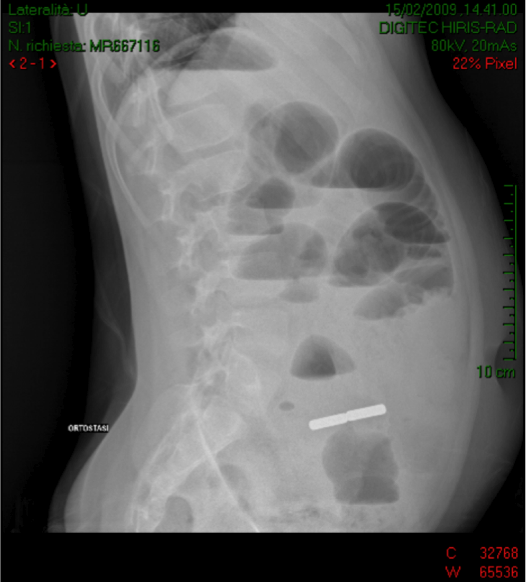

M.

viene mantenuto a digiuno e, per il peggioramento del quadro

addominale e la persistenza di vomito, viene ripetuta eco addome

che mostra marcata distensione delle anse del tenue, con presenza

di quota fluida endoperitonaeale, ed Rx diretta addome che mostra

un quadro di occlusione intestinale con livelli idroaerei e, in

fossa iliaca destra, la presenza di un'immagine “a

bastoncello”, duplice, della lunghezza totale di 5 cm, a

densità metallica (Figura 1). Al

![]()

Figura

1